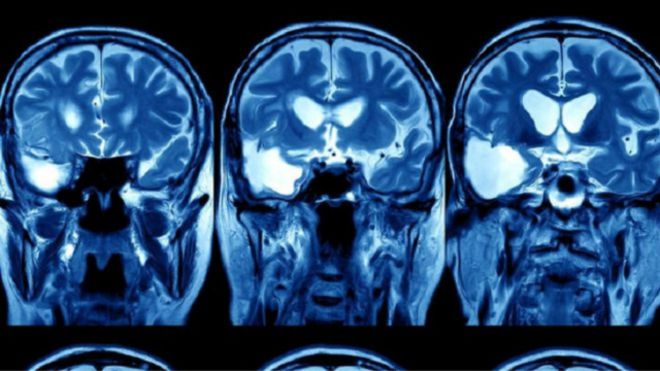

يعتزم مستشفى بريطاني استخدام نظام الذكاء الصناعي لجوجل، المعروف باسم “ديب مايند”، لتحليل صور الأشعة المقطعية وأشعة الرنين المغناطيسي لـ 700 مريض سابق في وحدة العلاج الإشعاعي لمرضى السرطان.

والهدف من الأمر هو تطوير معادلة حسابية تكنولوجية يمكنها بصورة أوتوماتيكية التمييز بين الأنسجة السليمة والأنسجة المصابة بالسرطان.